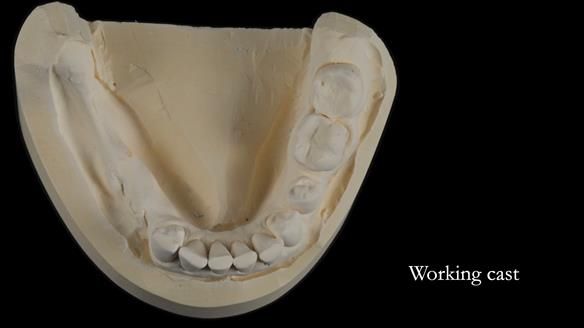

The detailed clinical situation and treatment process are outlined below, with clinical work provided by me and technical work by Rowan Garstang. The treatment spanned six visits for denture fitting and one review.